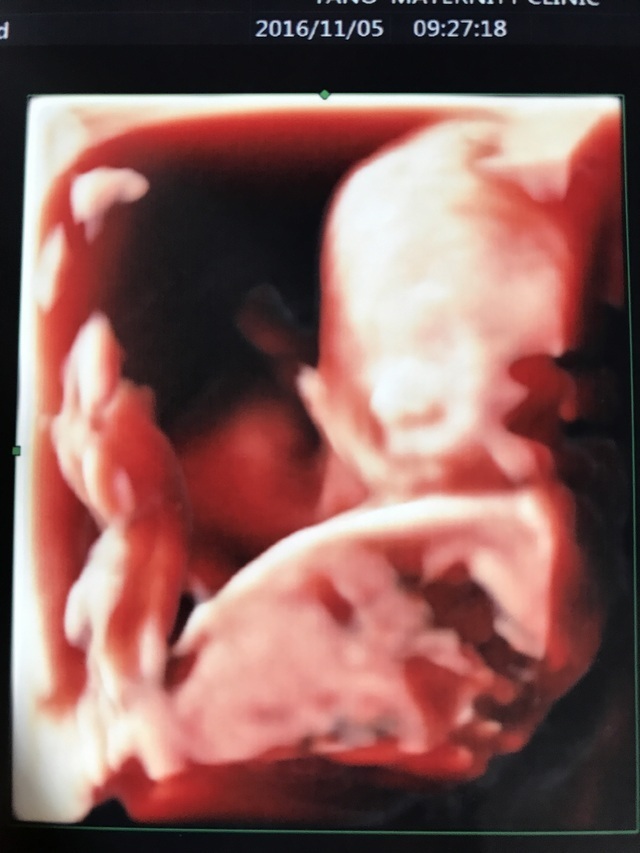

20週1日(20w1d・女の子)|acou さん(35歳)

4Dは自分の病院は2回しか見れないんです。やっと出来た赤ちゃんを初めて鮮明に見ることが出来た時の写真です。

今までエコーで見ても顔までよく見えなかったですが、この子がお腹にいるんだぁ、動いているなぁ、とかとにかく感動して4Dエコー中ずっと泣いてました(T_T)